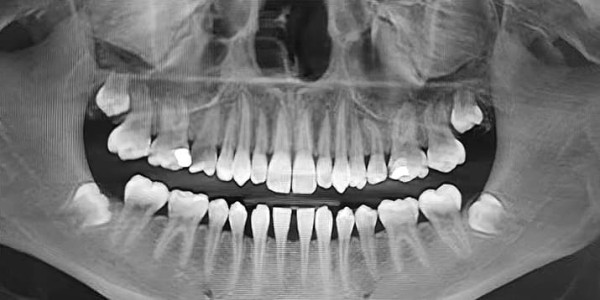

— На ортопантомограмме (см. рис. 2) видно, что зачатки третьих премоляров заложены глубоко, зачатки зубов 1.8 и 2.8 расположены близко к верхнечелюстным пазухам, 4.8 — к нижнечелюстному каналу. Чтобы удалить такие зубы, требуется весьма сложное травматичное вмешательство, как правило, под общим наркозом. При этом показаний для удаления нет, — прокомментировал Яков Тимчук.

Рисунок 2. Ортопантомограмма 15-летнего пациента с глубоко заложенными зачатками 8-х зубов.